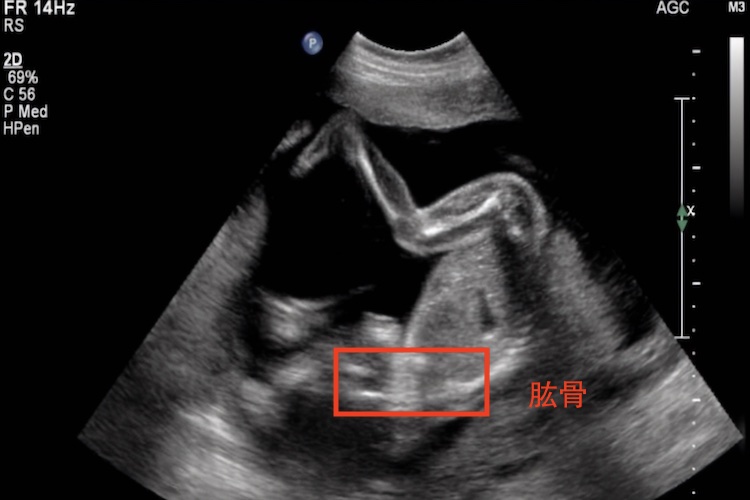

肱骨是胎儿的上臂,为上肢最大的管状骨,分为肱骨体及上下两端。

孕期通过测量胎儿肱骨、双顶径、股骨长度,可评估胎儿的大小。

临床通常借助B超测量胎儿的肱骨长度、胎头大小(测量胎头双顶径、胎儿头围)、股骨(大腿骨)长度,腹围,综合估计胎儿的大小。